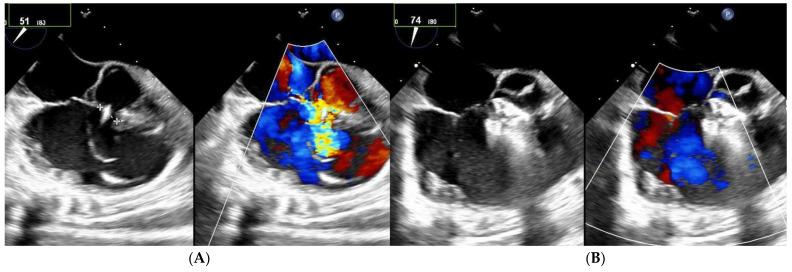

(1) Transcatheter closure of perimembranous ventricular septal defects (PmVSD) is becoming more attractive and effective with the development of new occluders. The aim of this study was to report a single-center experience in PmVSD closure using the Lifetech Konar-multifunctional occluder (MFO). (2) From March 2019 to October 2022, 43 consecutive patients were enrolled in the study. Among them, 13 had multifenestrated PmVSD including 5 Gerbode-type defects. (3) There were 23 males/20 females, and the median age was 17 years (range 2-68 years). Trivial aortic regurgitation was noticed in 19 patients. Implantation was successful in all patients under general anesthesia. A retrograde approach was used in 35 patients (81%). The retrograde approach was associated with a lower radiation dose ( = 0.042) and shorter fluoroscopy time ( = 0.002) compared to the antegrade approach. Full occlusion was observed immediately in 12 patients (28%) and in 33 patients (77%) at a median follow-up of 11 months. There were no complications such as embolization, complete atrioventricular block, device dislocation, new onset above grade I, or progression of tricuspid or aortic valve regurgitation. Seven of the thirteen patients with a multifenestrated defect had no residual shunt. The persistent shunts were all trivial intra-prosthetic leaks. (4) MFO is effective and safe for PmVSD closure including multifenestrated/Gerbode-type defects with no complication. However, a longer follow-up remains warranted to establish the safety of this technique.

(1) 随着新型封堵器的发展,经导管闭合膜周部室间隔缺损(PmVSD)正变得更具吸引力且更有效。本研究的目的是报告使用深圳先健科技公司的柯纳多功能封堵器(MFO)闭合PmVSD的单中心经验。(2) 从2019年3月至2022年10月,连续43例患者纳入本研究。其中,13例为多孔型PmVSD,包括5例Gerbode型缺损。(3) 男性23例/女性20例,中位年龄为17岁(范围2 - 68岁)。19例患者存在轻度主动脉瓣反流。所有患者均在全身麻醉下成功植入。35例患者(81%)采用逆行途径。与顺行途径相比,逆行途径的辐射剂量更低(P = 0.042),透视时间更短(P = 0.002)。12例患者(28%)即刻观察到完全封堵,在中位随访11个月时,33例患者(77%)达到完全封堵。未发生栓塞、完全性房室传导阻滞、封堵器移位、I级以上新出现的或三尖瓣或主动脉瓣反流进展等并发症。13例多孔型缺损患者中有7例无残余分流。持续性分流均为封堵器内轻度渗漏。(4) MFO用于闭合包括多孔型/Gerbode型缺损在内的PmVSD有效且安全,无并发症。然而,仍需要更长时间的随访以确定该技术的安全性。